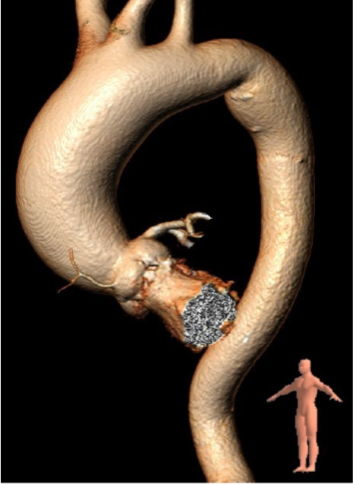

此患者解剖结构复杂:1)升主动脉明显增宽,平均直径达到54.5mm。

该结构需谨慎评估血管夹层和破裂风险,对瓣膜系统的通过性能要求极高。

2)患者主动脉根部结构复杂,为Type 2型二叶瓣畸形,左右对合缘、右无对合缘处均可见钙化融合嵴,瓣环平面可见严重钙化,左冠窦底钙化灶延伸至左室流出道,且左室腔小。

瓣叶钙化严重,且增厚增长。